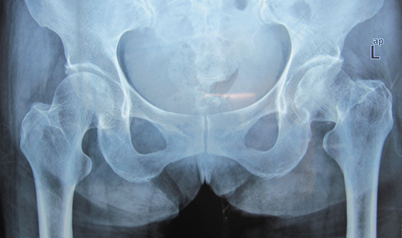

很多中老年人去做身体全面检查的时候,会被检查出患有股骨头坏死的情况,并且出现股骨头坏死的患者,在日常生活多方面都会受到影响,会影响患者正常的行走等肢体活动。那么,股骨头坏死怎么造成的?

股骨头的坏死可能是患者自身出现病变,身体受到外伤或是一些激素的刺激所导致的。像患者如果前期出现车祸,就可能会导致股骨头骨折,关节部位脱位或骨折等症状,后期就会引起股骨头部位出现坏死。

一般当患者股骨头部位的血管受到了损伤,或是出现断裂的话,股骨头就会出现坏死。因此,对于出现股骨头坏死的患者,要仔细找明患者股骨头坏死的原因,还要注意多注意,根据症状选择保守治疗或是手术治疗。